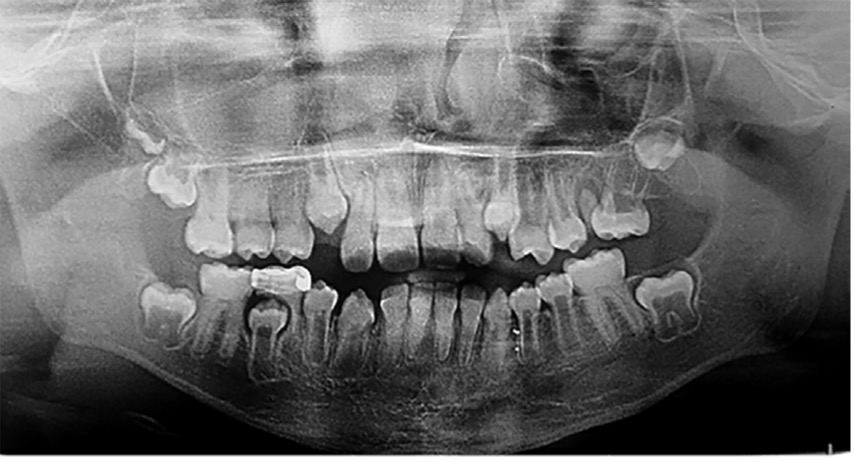

El examen clínico intraoral reveló alteración de la estructura y color de las piezas primarias, atrición y pérdida de la dimensión vertical (Figura 2). Radiográficamente se observó la presencia de coronas con marcada constricción cervical y raíces cortas (Figura 3). Presentaba alto riesgo cariogénico, por la presencia de lesiones de caries activas y dos restos radiculares, sumado a la anomalía estructural de la dentina (riesgo biológico específico) y bajo riesgo gingivoperiodontal. El riesgo socio-económico era alto por provenir de una familia con marcadas limitaciones económicas. Luego de la anamnesis, examen clínico y radiográfico, e interconsulta con el médico de cabecera se estableció el diagnóstico de DI Tipo I asociado a OI tipo I. Se planificó un tratamiento integral y preventivo con los objetivos de devolver forma y función, y proteger y evitar el desgaste de los tejidos conductas que pudieran interferir con el tratamiento.

Figura 3: Radiografía panorámica año 2007

En la radiografía panorámica de control del año 2015 se observó la progresiva obliteración del conducto radicular en el grupo incisivo superior e inferior y en los primeros molares permanentes; presentado los premolares en erupción, un conducto radicular anormalmente amplio en toda su longitud (Figura 8). En la del año 2018 se visualizó la continua aposición de dentina a nivel radicular que obliteró en forma casi total los conductos de la mayoría de las piezas dentarias, a excepción de los segundos molares inferiores (Figura 10).

Debido el alto porcentaje de abscesos periapicales, producto de la obliteración progresiva de los conductos radiculares, es fundamental el monitoreo radiográfico periódico en pacientes con DI.1 Los controles con radiografías panorámicas fueron realizados en el 2007, 2010, 2015 y 2018, sin registro de patologías pulpares periapicales.